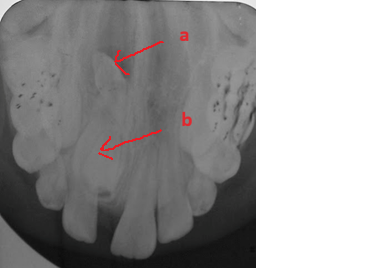

Mesiodents               Paramolar Distomolar(a), Paramolar (b)

Hình 1: Các loại răng thừa